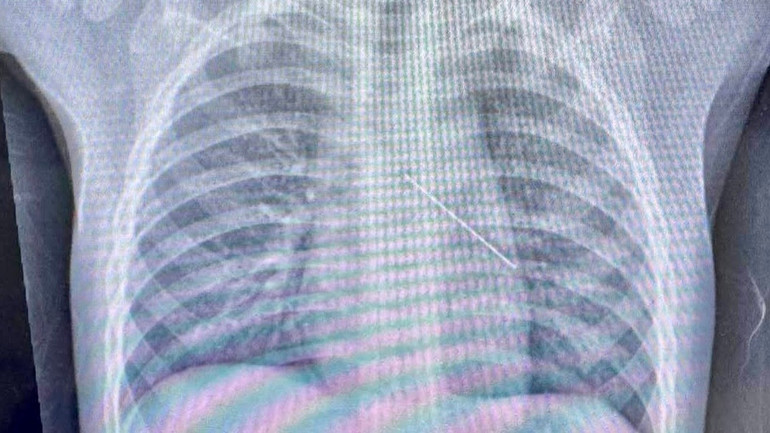

Hình ảnh chụp phim cho thấy rõ cây kim nằm trong phế quản bệnh nhi.

Tương tự, tại Bệnh viện Nhi đồng Thành phố vừa cấp cứu thành công một trẻ hơn một tuổi bị kim ghim đâm sâu vào phế quản. Bác sĩ cho biết, dị vật nằm trong đường thở rất nhỏ, nguy cơ nghẹt thở cận kề, nhờ kích hoạt quy trình cấp cứu khẩn và phối hợp nội soi kịp thời, ê-kíp đã gắp dị vật thành công, giúp trẻ thở lại an toàn.